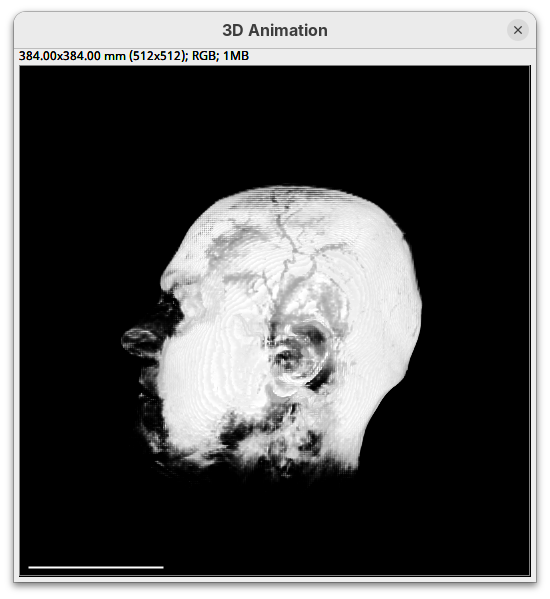

Two new windows will open: 3D Animation with the initial rendering of the data and Interactive Raycaster with all the fields to control the rendering parameters.

Contrast

You will see that the darkest parts of the rendering will become even darker and no longer visible. We are losing real information from the data; we do not want that.

The brightest parts of the rendering will become all white. It is so bright that we can no longer resolve details of the surface. We are losing information and also do not want that.

minto250.

This will make darker pixels more transparent and information gets lost.

Note that this improves the visualization as the head’s surface becomes better visible.